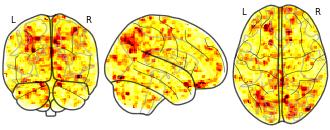

License information was derived automaticallyDescriptionGroup × Time interaction on PI-related brain activation in the Difficult-to-Name (DN) condition. Highlights regions where the relationship between statistical learning performance (PI) and brain activity differs between TD and DLD groups across pre- and post-training.

This dataset includes whole-brain statistical maps from a longitudinal fMRI study investigating visual statistical learning (SL) in children aged 6–9 years with developmental language disorder (DLD; n = 27) and typically developing (TD; n = 35) peers. Participants completed an SL task involving visual sequences under two stimulus conditions: easy-to-name(EN; animal drawings) and difficult-to-name (DN; abstract Hebrew letters). Sequences were either structured (1-back transitional probabilities) or random. Functional scans were collected at two time points: before and after one week of home-based SL training.

At the first-level analysis, individual contrast maps were computed comparing BOLD responses to structured vs. random sequences (Statistic > Random), separately for each stimulus type. At the second level, full-factorial SPM12 models (2 Group × 2 Time) were implemented separately for EN and DN conditions. Crucially, group-level models included four z-scored covariates representing individual performance index (PI) for each group and session, enabling the analysis of brain–behavior associations and their modulation by group and training. Additional analyses included F-tests on PI covariates (Group × Time interaction) and t-tests comparing group differences in PI-related activation at each time point.

All functional images were acquired on a 3T Siemens Prisma scanner. Preprocessing included motion correction, normalization to MNI space, and spatial smoothing (6 mm FWHM). Data quality control included framewise displacement scrubbing and a minimum tSNR threshold of 100.